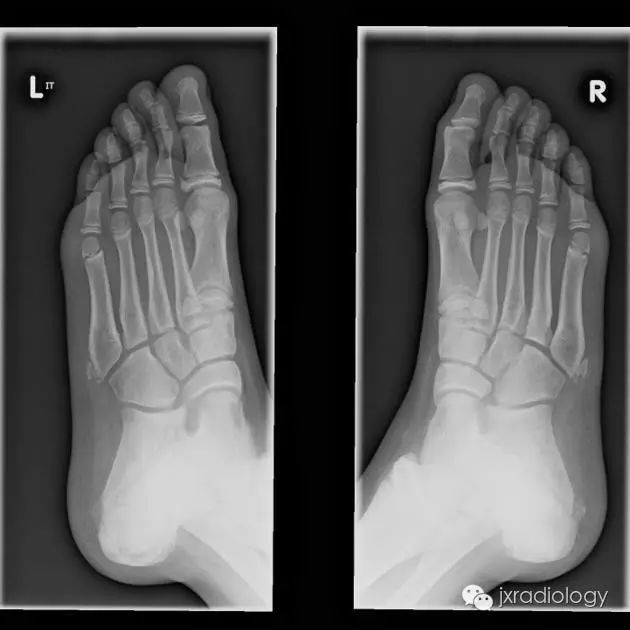

骨骺裂是一种正常变异。它可以是单侧或双侧,最常见的部位是足的第1趾近节趾骨的骨骺。

X线平片显示骨骺见透亮状裂隙影;透亮影的边缘是可变的,可能是锐利的或不规则的。骨骺裂可保留至生长板的融合。

X线平片将显示骨骺有透明缺损。透明度的边界是可变的,可能是尖锐的或不规则的。裂缝一直保持到生长板融合。

骨骺裂必须和骨折鉴别。一般骨折损伤2-3周后复查平片可见愈合的迹象。识别这个现象是重要的,以避免过度治疗和不必要的手术干预。

骨骺裂必须与骨折相鉴别。通常,如果在受伤后 2-3 周重复 X 线检查,骨折就会显示出愈合迹象。识别该实体对于避免过度治疗和不必要的手术干预非常重要。骨骺裂意译为骨骺裂,结合临床病史及复查才能和骨折区分。